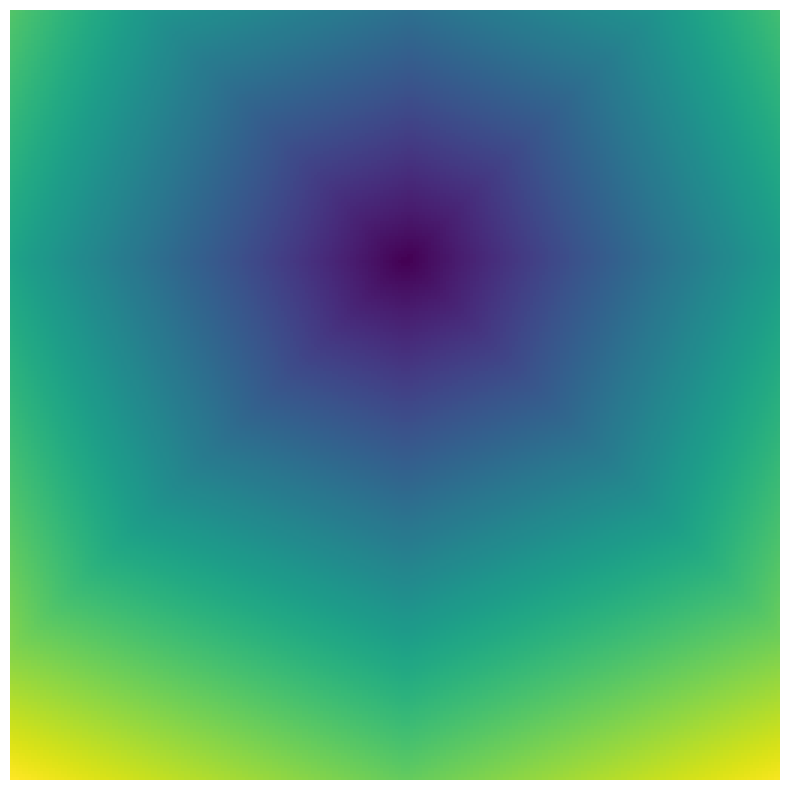

Generally, given an exact, full annotation of an object, such a Euclidean signed distance map encodes also information on the shape of an object. But when using a weak ground truth , where and , inferring a correct extent and shape of the objects is nontrivial. As shown in 1(b), Euclidean distance calculated from a point label source grows radially, regardless of the actual shape of the object, and thus makes little sense from an information point of view. Under the assumption of intra-object homogeneity and inter-object contrast (w.r.t intensities), this problem can be circumvented to a degree by using a distance function that takes also intensity values into account. An example of a commonly used distance measure with an intensity component is the Geodesic distance ([34]). Let denote a path between , with and being neighbors under a chosen adjacency relation. Reusing the notation from before, a Geodesic distance map from the boundary of the ground truth class , , can be defined as

Both the Intensity and the Minimum barrier distance are defined exclusively on the image intensity space. However, from the examples of distance map in 1(d), we can notice that the values still increase somewhat radially from the annotation. This behaviour is similar to the one of the Geodesic distance in 1(c) (which actually includes the spatial proximity in its definition), and is due to the summing operator in the general Geodesic distance definition in Equation 3. While the intensities of two neighboring pixels on a path may be the same, that will rarely be the case in real life, noise riddled images. This makes the Intensity distance function approximately monotonically increasing with increasing length of the path (in space), even on paths where the intensity is mildly fluctuating (e.g. consider a path with even pixels intensity value of and odd pixels intensity value of ). One could thus argue that such a definition of a distance, despite being based exclusively on intensities, is still capable of loosely encoding the spatial distance information.

On the other hand, while we can see that the MBD based maps are similar to Geodesic and Intensity ones (1(e)) with respect to the object shape recovery, they have a less pronounced and smooth increase in the values outward from the source point.

In contrast to Euclidean distance, the Geodesic, Intensity and Minimum barrier distance maps all encode contrast sensitivity and preserve the object structures by harnessing the intensity information of the underlying image. This holds even when calculated from point sources. In practice, using such maps for network training could mean a lower penalty for false positives that occur farther from the point annotation but are close to it in intensity. Thus still enabling the propagation of a sort of shape information (as it can be inferred from the raw image intensities).